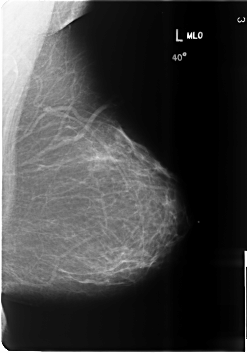

ics_version 1.0 filename B-3486-1 DATE_OF_STUDY 1 6 1998 PATIENT_AGE 39 FILM FILM_TYPE REGULAR DENSITY 1 DATE_DIGITIZED 4 6 1999 DIGITIZER LUMISYS LASER SEQUENCE LEFT_CC LINES 6016 PIXELS_PER_LINE 4128 BITS_PER_PIXEL 12 RESOLUTION 50 NON_OVERLAY LEFT_MLO LINES 6000 PIXELS_PER_LINE 4184 BITS_PER_PIXEL 12 RESOLUTION 50 NON_OVERLAY RIGHT_CC LINES 6024 PIXELS_PER_LINE 4144 BITS_PER_PIXEL 12 RESOLUTION 50 OVERLAY RIGHT_MLO LINES 6024 PIXELS_PER_LINE 4120 BITS_PER_PIXEL 12 RESOLUTION 50 OVERLAY |